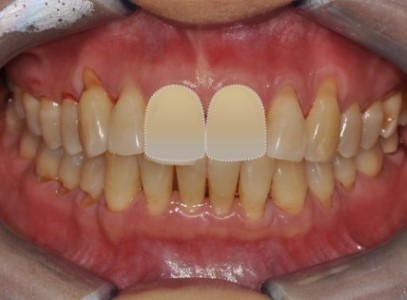

보철 전 교정치료 - 앞니 벌어짐 개선